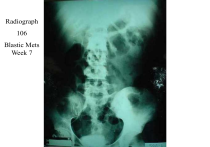

Radiograph 106 Blastic Mets Week 7 Radiograph 960 Lytic Mets Week 7 Radiograph 961 Blastic Mets Week 7 Radiograph 962 Mixed Mets Week 7 Radiograph 963 Lytic Mets Week 7 Top image 4- months prior to bottom image